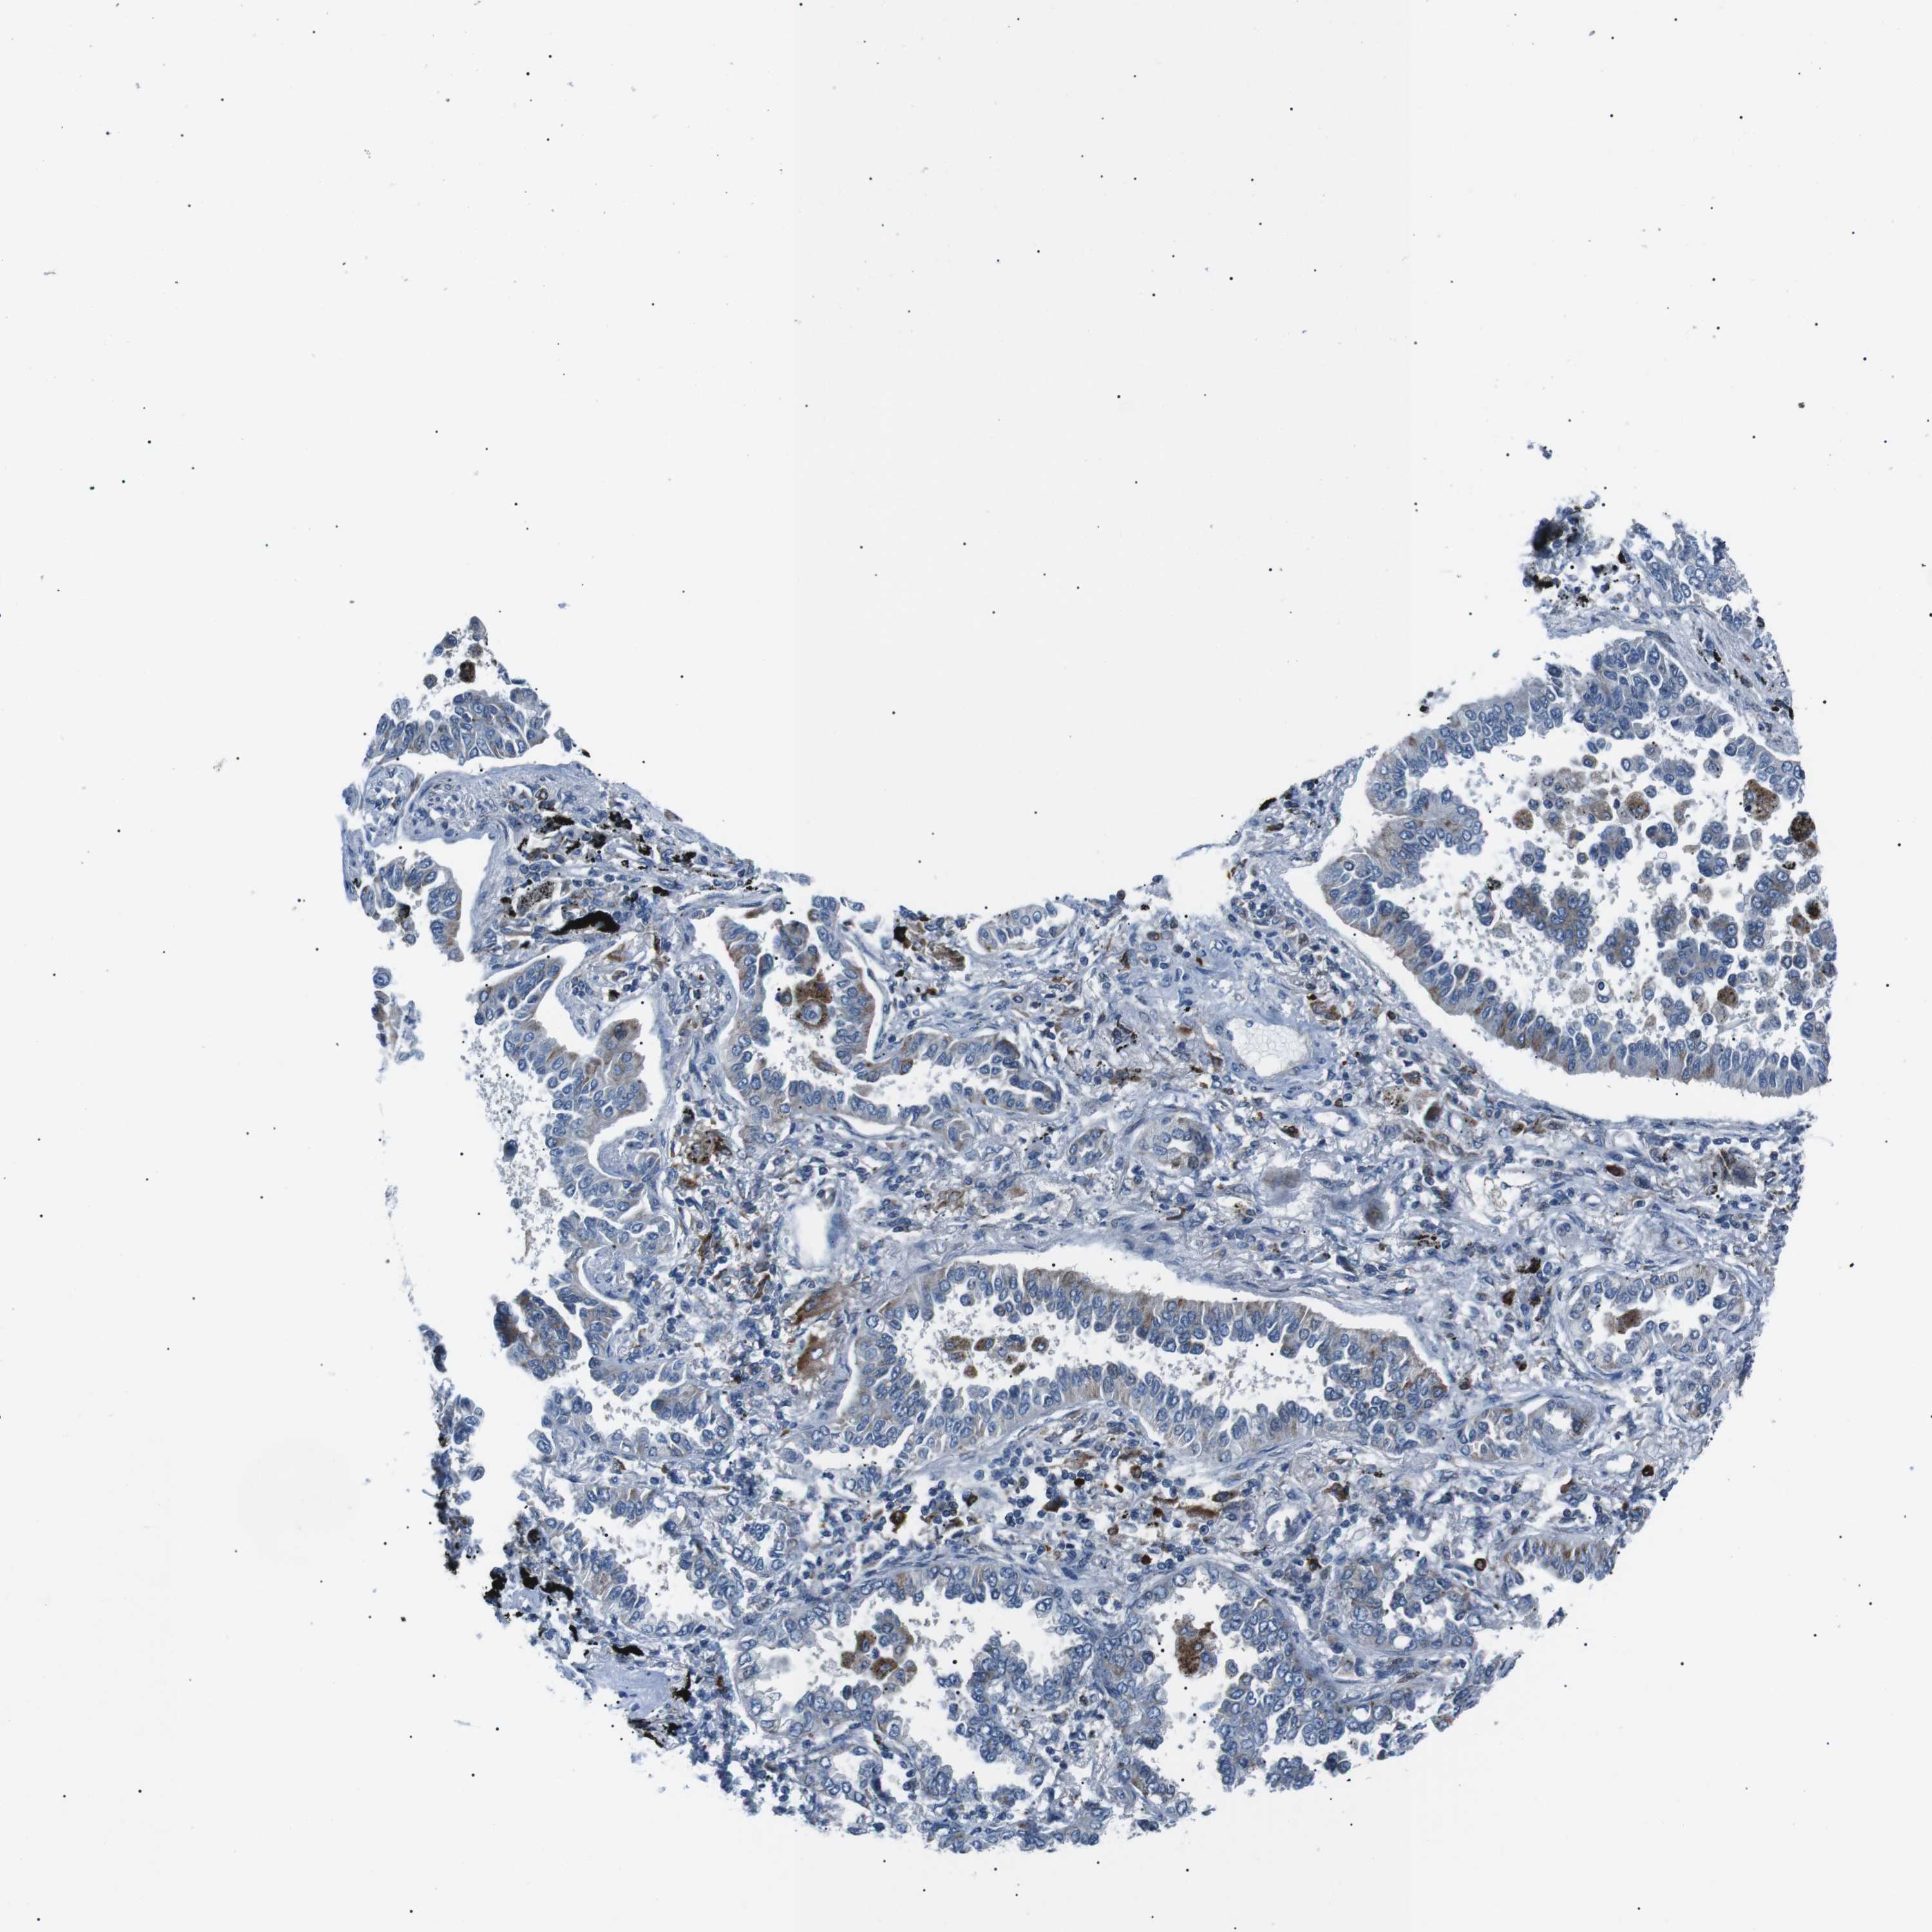

CANCER LUNG CANCER Show tissue menu

LUAD TCGA LUAD VALIDATION LUSC TCGA LUSC VALIDATION PROTEIN LUAD CPTAC PROTEIN LUSC CPTAC PROTEIN EXPRESSION

ANTIBODIES

AND

VALIDATION